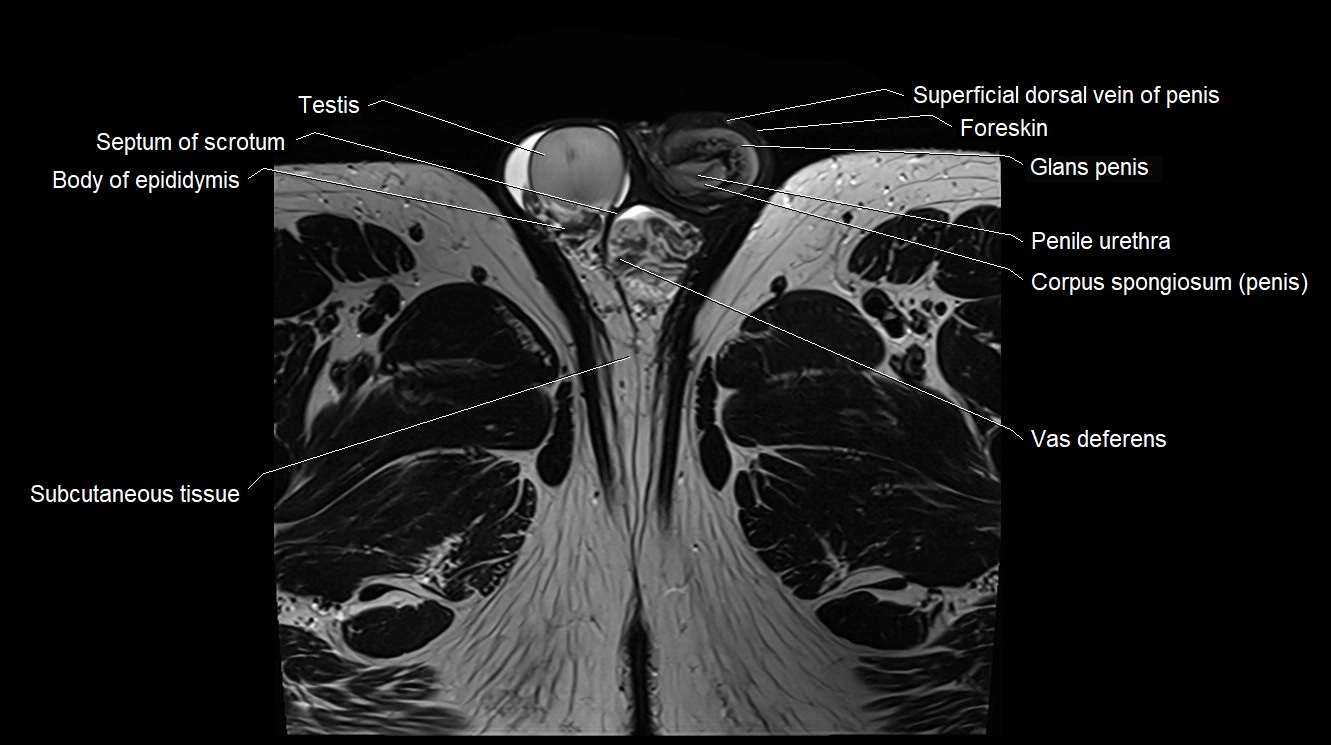

- Body of epididymis

- Cremaster fascia

- Foreskin

- Glans penis

- Penile urethra

- Scrotal fluid

- Septum of scrotum

- Skin of scrotum

- Superficial dorsal vein of penis

- Testis

- Vas deferens